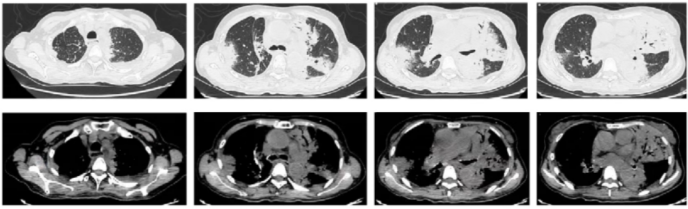

患者4月6日入院时肺部大面积实变,7月6日(气管切开封口)复查胸部CT可见病灶明显吸收(图3),7月8日患者康复出院。

图片

图3  患者从入院到康复的影像学变化